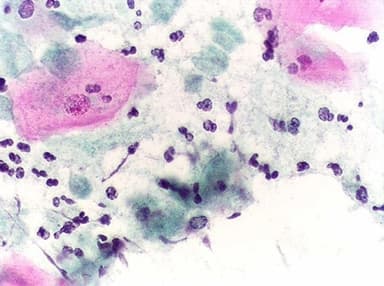

Viêm cổ tử cung

Bệnh viêm cổ tử cung có thể xử trí được nếu phát hiện sớm. Tuy nhiên, nếu bệnh không được xử trí kịp thời sẽ gây ra nhiều biến chứng nguy hiểm đối với sức khỏe đặc biệt là sức khỏe sinh sản của chị em.

Viêm cổ tử cung chủ yếu là do sự xâm nhập của các vi khuẩn, virus gây bệnh. Các vi khuẩn, virus xâm nhập vào cổ tử cung gây bệnh qua nhiều con đường khác nhau. Nữ giới sinh hoạt tình dục bừa bãi, không an toàn, thô bạo dễ làm tổn thương cơ quan sinh dục, tạo điều kiện thuận lợi cho vi khuẩn xâm nhập và gây bệnh. Bên cạnh đó, việc vệ sinh vùng kín đặc biệt là sau khi giao hợp, trong chu kỳ kinh nguyệt không đảm bảo cũng là nguyên nhân gây bệnh viêm âm đạo. Những chị em có tiền sử nạo phá thai, sinh con sớm là những đối tượng có khả năng mắc viêm cổ tử cung cao hơn nhiều lần so với những người bình thường.

Viêm cổ tử cung cản trở quá trình gặp trứng của tinh trùng do viêm nhiễm nên gia tăng nguy cơ vô sinh, khi quan hệ không có cảm giác thỏa mãn, làm giảm chất lượng đời sống tình dục.